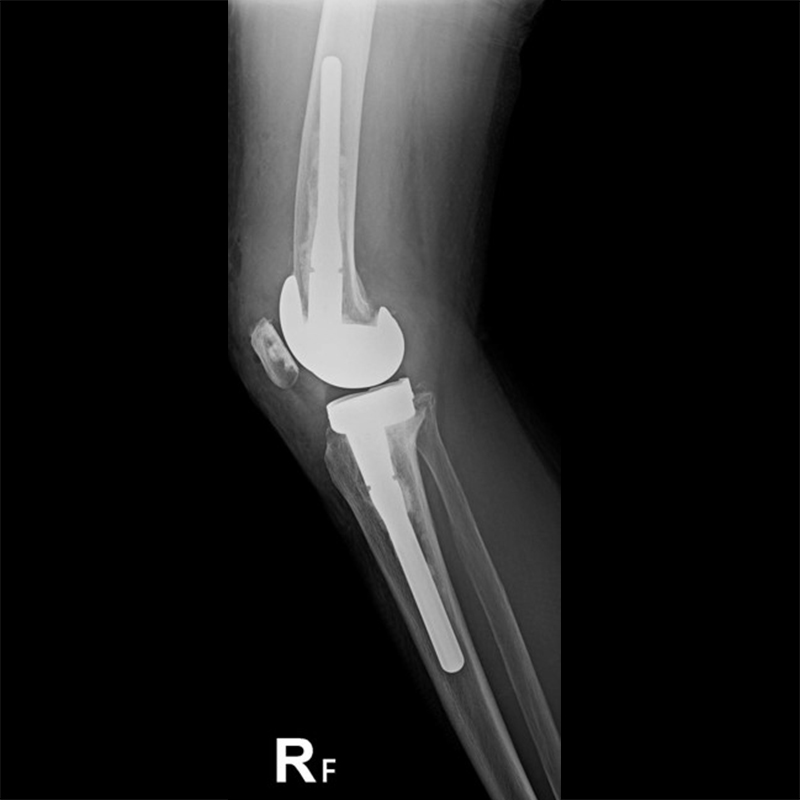

外院失敗本院再置換 首頁 案例分享 膝關節手術 外院失敗本院再置換 蕭女士 69歲 術前 術後 81歲 林女士 術前 術後 蕭女士 69歲 術前 術後 鄒女士 69歲 術前 術後 李女士 74歲 術前 術後 吳女士 71歲 術前 術後 謝女士 65歲 術前 術後